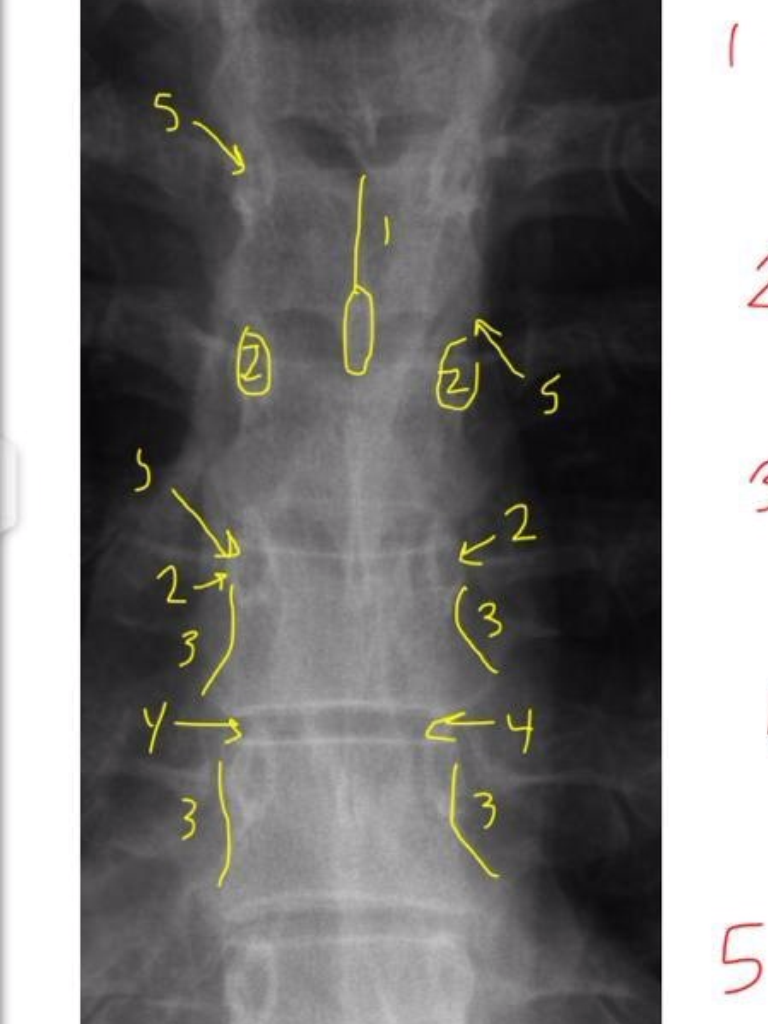

Q

1

A

Junction of laminae

(spinous tips)

20

2

Pedicle Shadows

21

3

vertebral waist

(biconcave aspect of body)

22

4

Disc Spaces

(not disc itself)

23

5

Endplate Tips

(vertebral body)